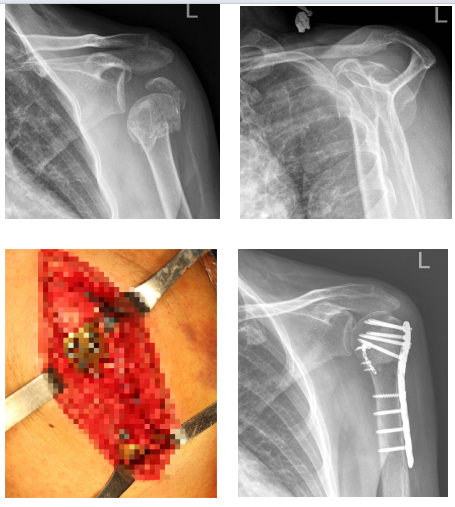

特色技术项目——髓内支撑钢板治疗肱骨近端粉碎性骨折

首席专家:肩肘外科负责人 王义隽

项目简介:团队提出“由内而外、先核后壳”理念,采用髓内支撑钢板结合外侧锁定钢板构建三维稳定系统,有效处理Neer 4型粉碎性骨折。该术式可在同一切口完成肩袖修复与骨折复位,保留血供与肌腱功能,术后关节功能恢复良好,并发症少。